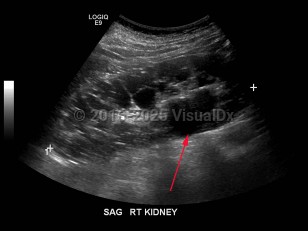

Polycystic kidney disease

Polycystic kidney disease (PKD) is an autosomal dominant (or, less often, autosomal recessive) disorder characterized by numerous cysts in the kidneys, which may lead to end-stage renal failure. The autosomal dominant trait is associated with mutations in either PKD1 (which encodes polycystin-1) or PKD2 (which encodes polycystin-2). A minority of patients with PKD have a defect unrelated to PKD1 or PKD2. PKD1 mutations are more common and correlate with an earlier age of disease onset as well as more rapid decline in renal function.

Patients with autosomal dominant inheritance usually manifest symptoms at around 30 years of age; symptoms include abdominal pain, hematuria, and high blood pressure. Hypertension is very common and precedes the onset of overt renal dysfunction. Complications specific to renal cysts include cyst rupture, cyst infection, and nephrolithiasis.

Patients may develop brain aneurysms and liver cysts. Typically, this has a strong familial pattern, and the risk of cerebral aneurysm in patients with PKD is highest in those who have family members who have had aneurysms.